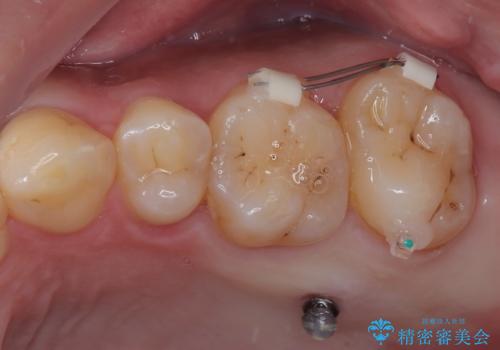

上顎の歯をアンカースクリューを用いた部分矯正により位置を修正し、根管治療後にPGAクラウンにて補綴治療を行うこととしました。

歯列が整ったことで咬み合わせが非常に安定しました。